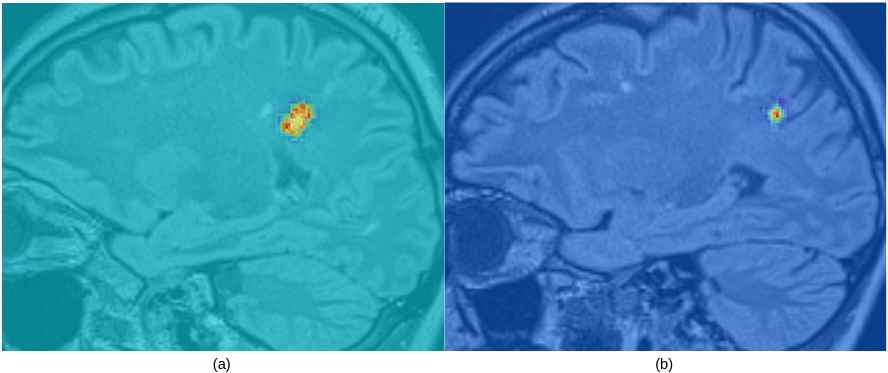

Examples of a slice in the sagittal plane of the 3D XAI maps generated from a TP and a FP are illustrated in Fig. 4. The LR output probability (relative to the TP class) for the TP lesion was 0.9398, and 0.0232 for the FP. The example FP candidate is located at the boundary between WM and cortex, and corresponds to one of the brain sulci.

Refer to caption

Figure 4: An example of a slice in the sagittal plane from a saliency map computed on a true (a) and false (b) positive lesion, scoring 0.9398 and 0.0232 for the true positive class.